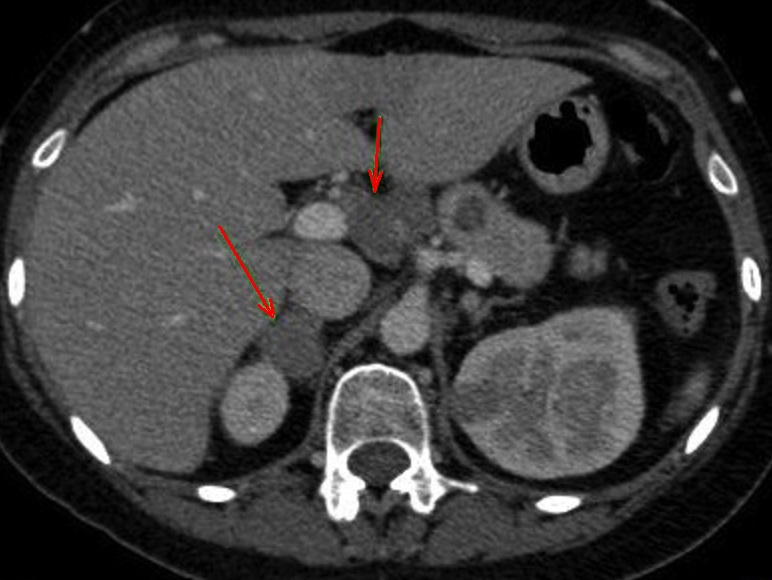

Meme cas en

coupe coronale |

Image radiologique TDM d'une

lymphome pancreatique a aspect lesionnel en forme

nodulaire hypodense , homogene situe au queu du

pancreas ( fleche rouge ) . |

|